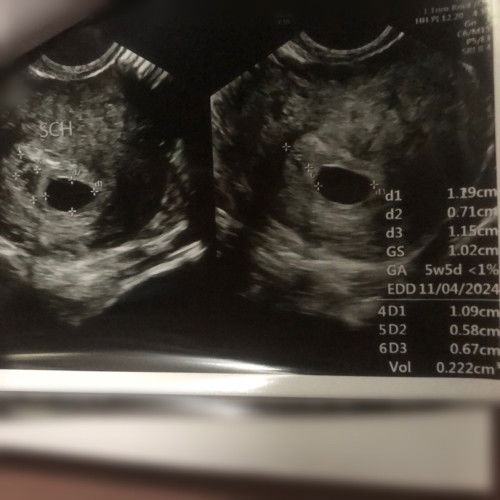

5weeks & 5days may gestational sac, walang yolk sac at embryo.

Normal lang po ba to? May pag asa pa po ba madevelop ang baby? Pls help po.πŸ™πŸ» super worried talaga ako.😒 #firstimemom #1sttrimester